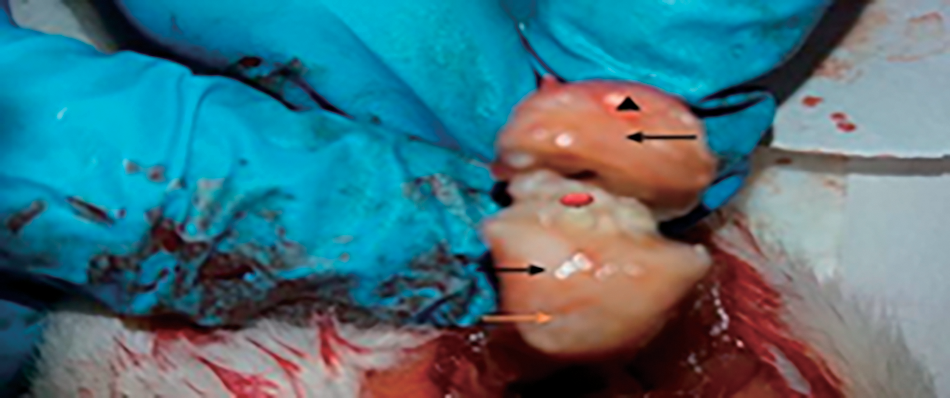

Results on OA rats showed the articular cartilage surface degradation, dense fibrous tissue, destruction and punctuate depression, erosion, glossy surface, and bone destruction of OA knee joints compared with OA treated with vitamin D3 and control rats which appeared with normal cartilage surface, smooth and intact, in addition, the pictures revealed to normal patella and normal tendon on articular cartilage region of treated rats with vitamin D3 compared to control pictures, (Figs. 5–7).

Fig 5. Showed two condyles from (OA) knee joint (), moderate degradation (), mild erosion () and dense accumulation of fibrous tissue ().

Fig. 6. Macroscopic observation in (OA) rat model showed knee joint, severe destruction and destruction () of articular cartilage surface, rough and irregular separation () between the condyles.

Fig. 7. Image on knee joint from treated rats with vitamin (D3) showed normal patella () and normal tendons ().